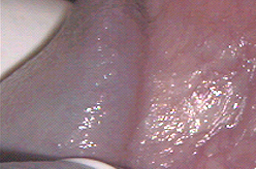

Desde hace muchos años se ha observado que si la piel infectada por Virus del Papiloma Humano (piel con lesiones o infectada) es destruida, se regenera con piel sana y el paciente puede eliminar la infección con una tasa de éxito variable dependiendo del tipo de aparato usado, y de la mejora que se obtenga en el sistema inmunológico de cada paciente.

El mejor aparato actualmente que nos permite medir y regular con precisión la profundidad de la piel que se desea destruir o la piel infectada es el LASER CO2, cuando es utilizado por un colposcopista experto,(el cual se adquiere cuando un ginecólogo realiza el entrenamiento en colposcopía por seis meses en una Clínica de Displasias), y capacitación técnica en el manejo del laser CO2. Ya que los tratamientos deben tener una profundidad menor a 1 mm (800 micras máximo) para que no afecten las terminaciones nerviosas y por lo tanto no dejen secuelas. Su aplicación se hace bajo anestesia local por lo que es indolora. Su tasa de éxito es alta, del 89% con recaídas del 8% durante los primeros 2 años. Por lo que actualmente es el mejor tratamiento para el Virus del Papiloma Humano y las lesiones precancerosas de genitales externos, vagina y las lesiones extensas en cérvix, (extensión de lesiones a fondos de saco vaginales). Aclarando que la tasa de éxito depende de la capacitación del médico que lo aplica, existen estudios en que la tasa de éxito es incluso del 50% debido a la mala técnica utilizada.